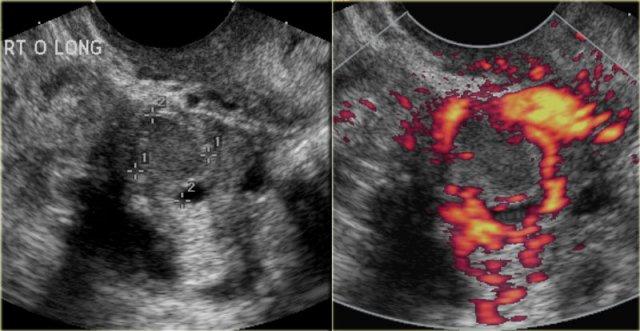

Hoàng thể có thể bị bít lại và chứa đầy dịch hoặc máu, tạo thành nang hoàng thể.

Các hình ảnh siêu âm qua ngã âm đạo cho thấy một nang buồng trứng phức tạp nhỏ với mạch máu thành nang trên phân tích Doppler năng lượng.

Hình ảnh Doppler vòng tròn đặc trưng này được gọi là dấu hiệu ‘vòng lửa’ (ring of fire).

Lưu ý, có hiện tượng xuyên âm tốt và không có mạch máu bên trong, phù hợp với nang hoàng thể đang thoái triển một phần.

Một trường hợp khác với hình ảnh điển hình của dấu hiệu ‘vòng lửa’ trên siêu âm.

Trên tiêu bản giải phẫu bệnh, nang xuất huyết xẹp có thể được quan sát rõ ràng.